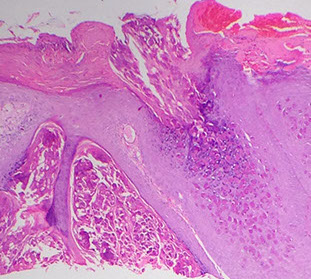

Blistering Dermatopathology

Vesiculobullous Dermatitis

Characterized by the location of the bulla

Bullous Pemphigoid (BP)

Pruritic, blistering autoimmune skin disorder c IgG abs to hemidesmosomes (BPAg1 and BPAg2)

- forms tense blisters on the extremities and trunks of older pts

- less severe than pemphigus vulgaris

*** "Pemphigoid" is longer than "pemphigus", "Hemidesmostome" is longer than "Desmosome" ***

Micro: Subepidermal blister (bullae) c eos and sometimes neutros in blister cavity

- can see eos lined up on DE junction in urticarial lesions

IF: Direct IF in perilesional tissue shows IgG and C3 on DE junction (basement membrane) in linear or n-serrated pattern

- Indirect has positivity on the roof of the lesion (vs on the floor in epidermolysis bullosa acquisita)

Bullous pemphigoid